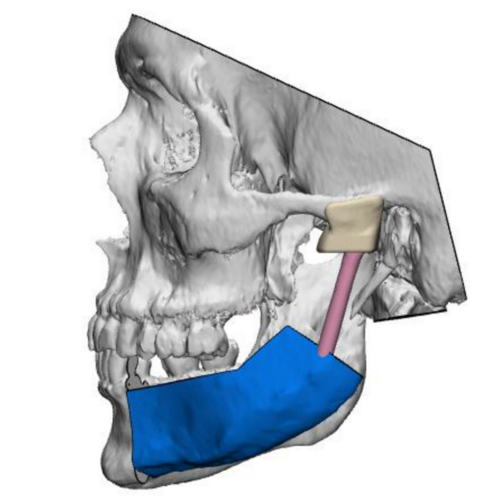

Jednym z najbardziej skomplikowanych zabiegów z przeprowadzonych w Klinice była rekonstrukcja stawu skroniowo-żuchwowego z wykorzystaniem materiału alloplastycznego, wykonanego w technologii druku 3D. W tym przypadku dodatkowo zastosowano płat biodrowy kostno-mięśniowy, pobrany za pomocą szablonu przygotowanego indywidualnie dla pacjenta. To rozwiązanie otwiera nowe możliwości leczenia pacjentów z nowotworami w obrębie części twarzowej czaszki, znacząco poprawiając ich jakość życia.